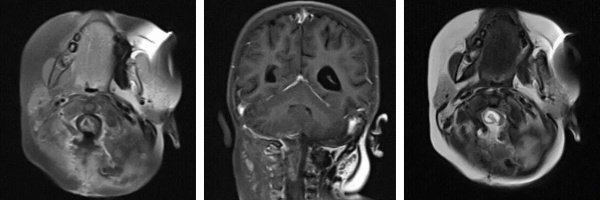

术后影像(MRI)

然而术后恢复之路仍充满波折。因并发脑积水,患儿出现呕吐等症状,经脱水治疗效果不佳。医疗团队与家属充分沟通后,再次为阿什利施行脑室-腹腔分流术,术后脑积水显著改善。与此同时,医院为她制定并实施了系统化疗方案,历经5个周期的药物调整与精心治疗,至今年7月MRI复查显示术区强化灶已完全消失。